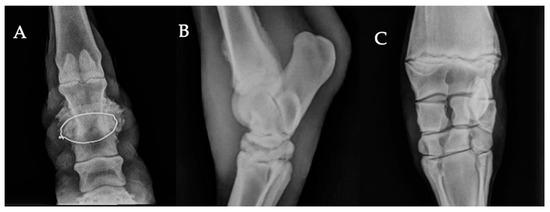

Common Radiographic Findings in Moroccan Working Equids: A Retrospective Study (2015–2022)

Working equids are at high risk of musculoskeletal disorders due to strenuous labor, repetitive tasks, and harsh environmental conditions. This retrospective study describes the distribution of radiographically detected musculoskeletal findings in working equids presented to four Society for the Protection of Animals Abroad (SPANA) centers in Morocco, based on 498 animals and 1125 radiographs collected between 2015 and 2022. The study population was mainly composed of horses (78.1%), followed by donkeys (15.3%) and mules (6.6%). Most were males (65.7%), and the majority were between 5 and 15 years old (60.4%). The distal limb (foot, pastern, and fetlock) was the most frequently examined region (62.7%). Among the animals reviewed, 381 (76.5%) exhibited at least one radiographically detected abnormality, while 117 (23.5%) showed no visible osseous change. The most frequent findings included foot-related changes (36.2%), defined as non-fracture podiatric abnormalities, fractures (29.7%), and periosteal new bone formation (22%). Less frequent findings were degenerative joint disease (8.1%), joint subluxation or luxation (1.6%), epiphyseal abnormalities (1.6%), and angular deformities (0.8%). These results provide an overview of radiographically detected osseous changes in working equids under field conditions. They highlight the diagnostic value of radiography in low-resource environments and provide a basis for future field-based studies. Full article

Figure 1